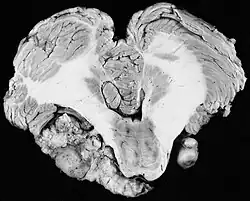

In the early 1900s the mortality rate for VS surgery was in the range of 75 to 85%. Surgeons typically delayed invasive intervention as long as possible as a last resort. Harvey Cushing (1869–1939) is known as 'the father of neurosurgery for VS.' His basic study published in 1917 was entitled Tumors of the Nervus Acusticus and the Syndrome of the Cerebellopontine Angle. Cushing perfected the retrosigmoid surgical approach, and by doing suboccipital craniotomy and subtotal removals he was able to reduce mortality to 4% by 1931. Cushing worked at Brigham Hospital in Boston. An equally famous specialist for VS at Johns Hopkins in Baltimore was Walter E. Dandy (1886–1946), a former pupil of Cushing who advocated total tumor removals. In 1931, he reported a complete removal with preservation of the facial nerve.

A major problem for the pioneers in VS neurosurgery was the lack of adequate imaging for spotting small tumors. Treating tumors that grew overly large in the cerebellopontine angle resulted in poor outcomes for the goals of facial nerve and hearing preservation. For imaging, conventional X-rays began to be used in the 1920s and CT scanners were introduced in the 1960s, but all were superseded by 'gold standard' MRIs in the 1980s. Facial nerve monitoring was added in 1979. William F. House (1923–2012) pioneered the use of the operating microscope, and (with William Hitselberger) popularized the translabyrinthine and middle fossa surgery approaches for VS. The operating microscope would be used in virtually all operations by 1998. House's son, John W. House, proposed (1983) and, with Derald E. Brackmann, developed the House-Brackmann grading system for reporting facial nerve outcomes following VS surgery.